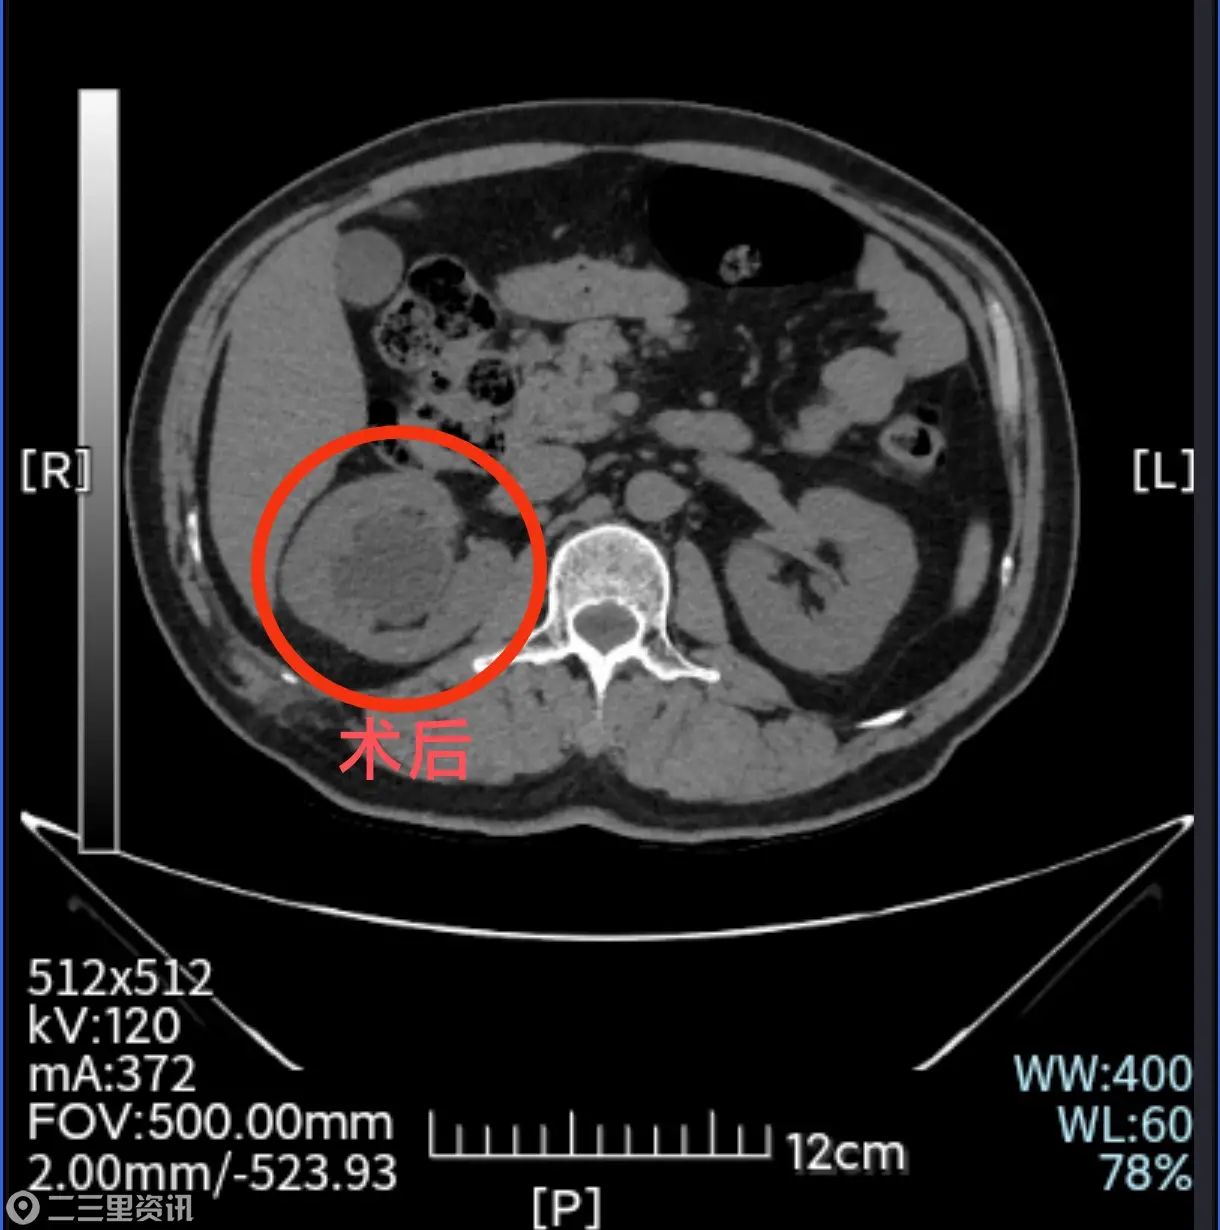

随后泌尿外科结石组张少杰团队为于先生实施了“无管化”的经皮肾镜激光碎石取石术(tubeless PCNL),手术创口仅1厘米,术中缝合一针并贴上创可贴,次日于先生即可正常下床活动,复查显示结石已彻底清除,对此于先生感觉非常满意,入院4天后即康复出院。

张少杰介绍,传统经皮肾镜术后要留置一根“管子”(肾造瘘管),外挂一个尿液引流袋(俗称“尿袋”),患者术后带着管子、袋子绝对卧床3日,从入院到手术康复一般需要一周左右时间,而当前科室成熟开展的“无管化”的经皮肾镜取石术后的“无管化率”已达60%,比肩国内顶尖医院结石治疗技术,该技术将传统手术带来的不适一扫而光,患者手术创伤小、住院时间短、身上也无任何管道束缚,治疗便捷性、舒适度极大提高。